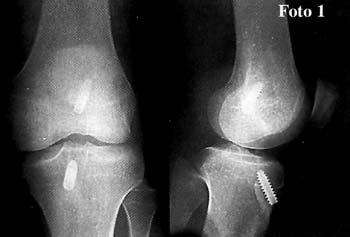

Fotos 1 y 2

El promedio de edad fue de 30 arios (rango entre 18 y 45 anos); distribucion por sexo, 218 sexo masculino y 54 femenino.